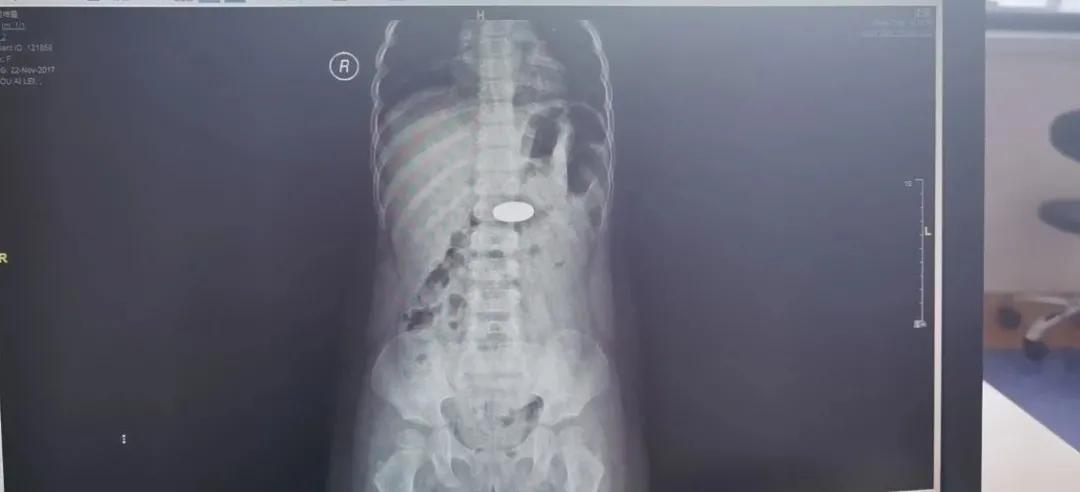

原来,在五天前,2 岁女童彤彤(化名)玩耍时不慎将一枚直径 25 毫米的一元硬币吞食。家长见状后,立马将孩子送到山东医专第一附属医院。经医生拍片诊断,硬币已经到了孩子的胃部。一般 2 岁及以上的孩子吞食硬币之类的杂物时能够自行排除,医生详细沟通并指导家长如何帮助孩子科学自然地排出吞食的硬币。但是5 天后,彤彤胃中的硬币仍未排出。